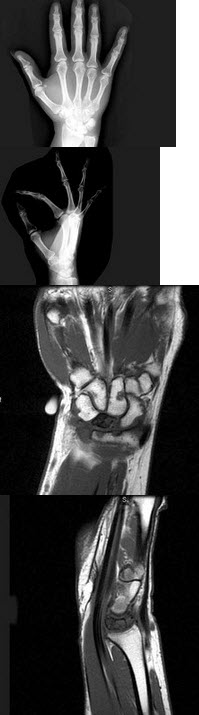

258、单项选择题

女,41岁,纺织工,腕部疼痛无力数周,结合CR和MR,最可能的诊断是()

A.月骨结核

B.月骨缺血坏死

C.骨质疏松

D.骨髓炎

E.骨软骨炎